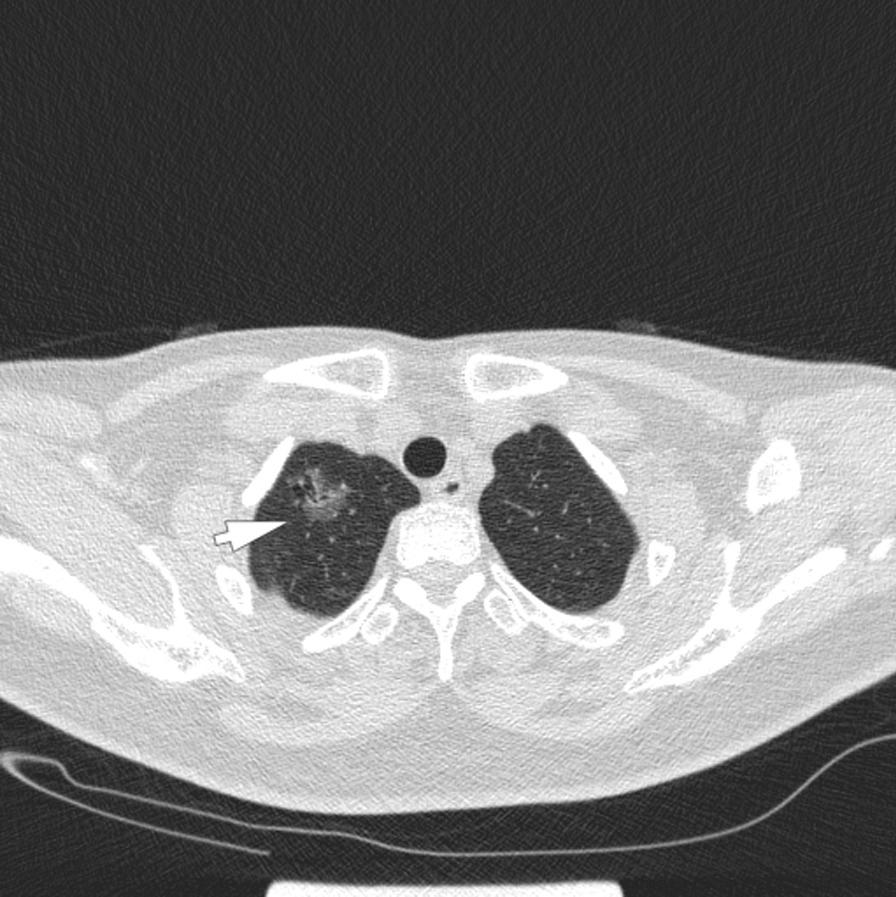

The patient was a 52-year-old female with recurrent cough for 3 months. Chest CT examination revealed a ground glass nodule of 17 * 23 * 18 mm in the right upper lung, and 3 new pulmonary nodules appeared around it 2 months later. The patient underwent right upper lobe lobectomy and pathology confirmed that the primary 2-cm-lesion in the right upper lobe was invasive lung adenocarcinoma, and two of the three surrounding lung nodules were pathologically suggestive of pulmonary fungal infection (not known in specific fungal types). Hence, the patient received empirical anti-fungal treatments with fluconazole 400 mg/day for a week and follow-up CT scanning showed no tumor progression and no relapse of fungal infection. The specific pathogen was eventually identified as Papiliotrema flavescens by the next-generation sequencing of pathogen.

患者为 52 岁女性,反复咳嗽 3 个月。胸部 CT 检查显示右肺上叶 172318mm 磨玻璃结节,2 个月后周围出现 3 个新的肺结节。患者接受了右上肺叶切除术,病理证实右肺上叶 2cm 原发性病变为浸润性肺腺癌,其中 3 个周围肺结节中的 2 个病理提示肺部真菌感染(具体真菌类型不详)。因此,患者接受氟康唑 400mg/天经验性抗真菌治疗 1 周,随访 CT 扫描显示肿瘤无进展,真菌感染无复发。通过病原体下一代测序最终确定病原体为黄灰孔菌。